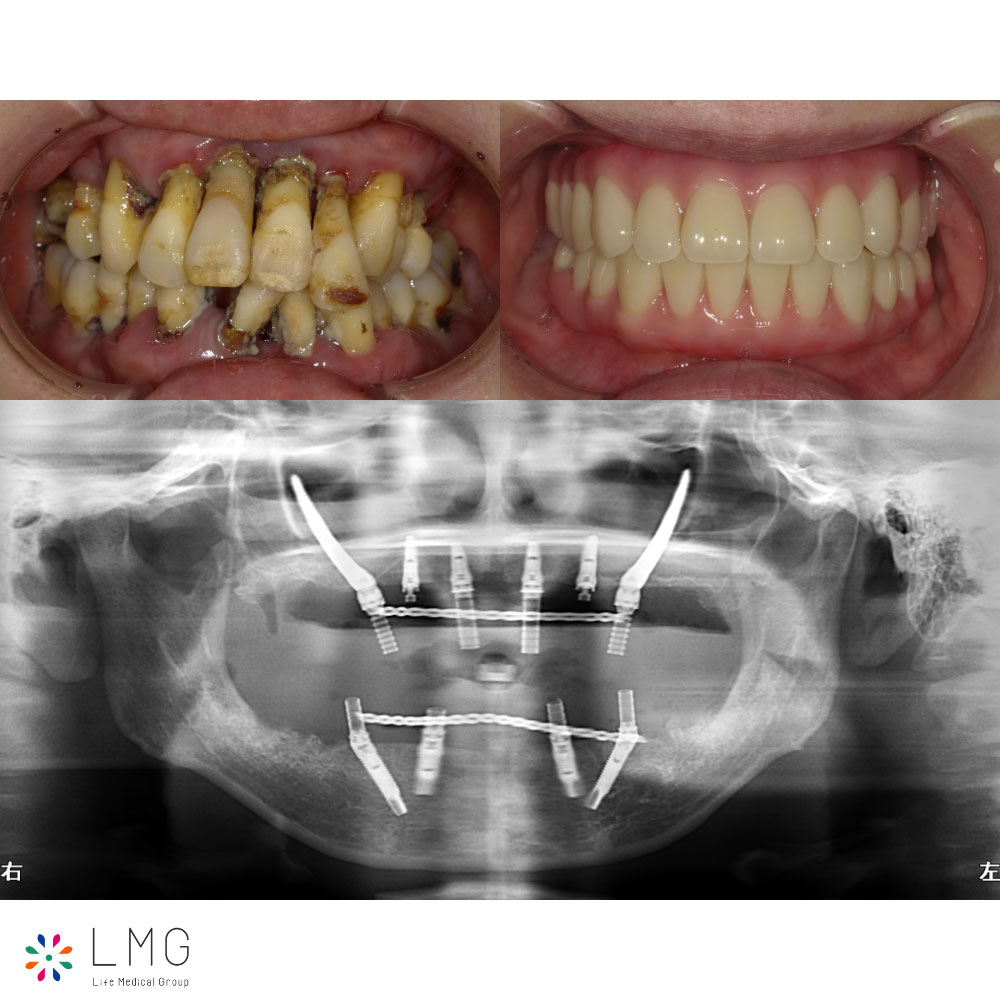

クワッドザイゴマを用いた上顎インプラント治療(全身麻酔あり) 「ザイゴマインプラント治療」を行われた患者さまのビフォーアフターをご紹介します。 ※ご紹介している症例は、あくまでも患者様固有の症例ですので、実際には患者様に […]